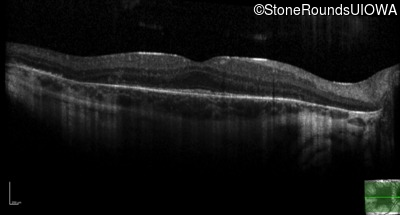

Optical Coherence Tomography - Left - 20/32 -2

Exemplar / OCT Stack